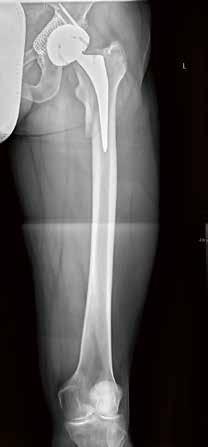

59-jähriger männlicher Patient mit Z.n. periprothetischer Fraktur nach Hüft-TEP; Abb. links: Oberschenkelaufnahme in Stitching-Technik zur präoperativen Planung, Abb. rechts: Post-OP-Dokumentation.